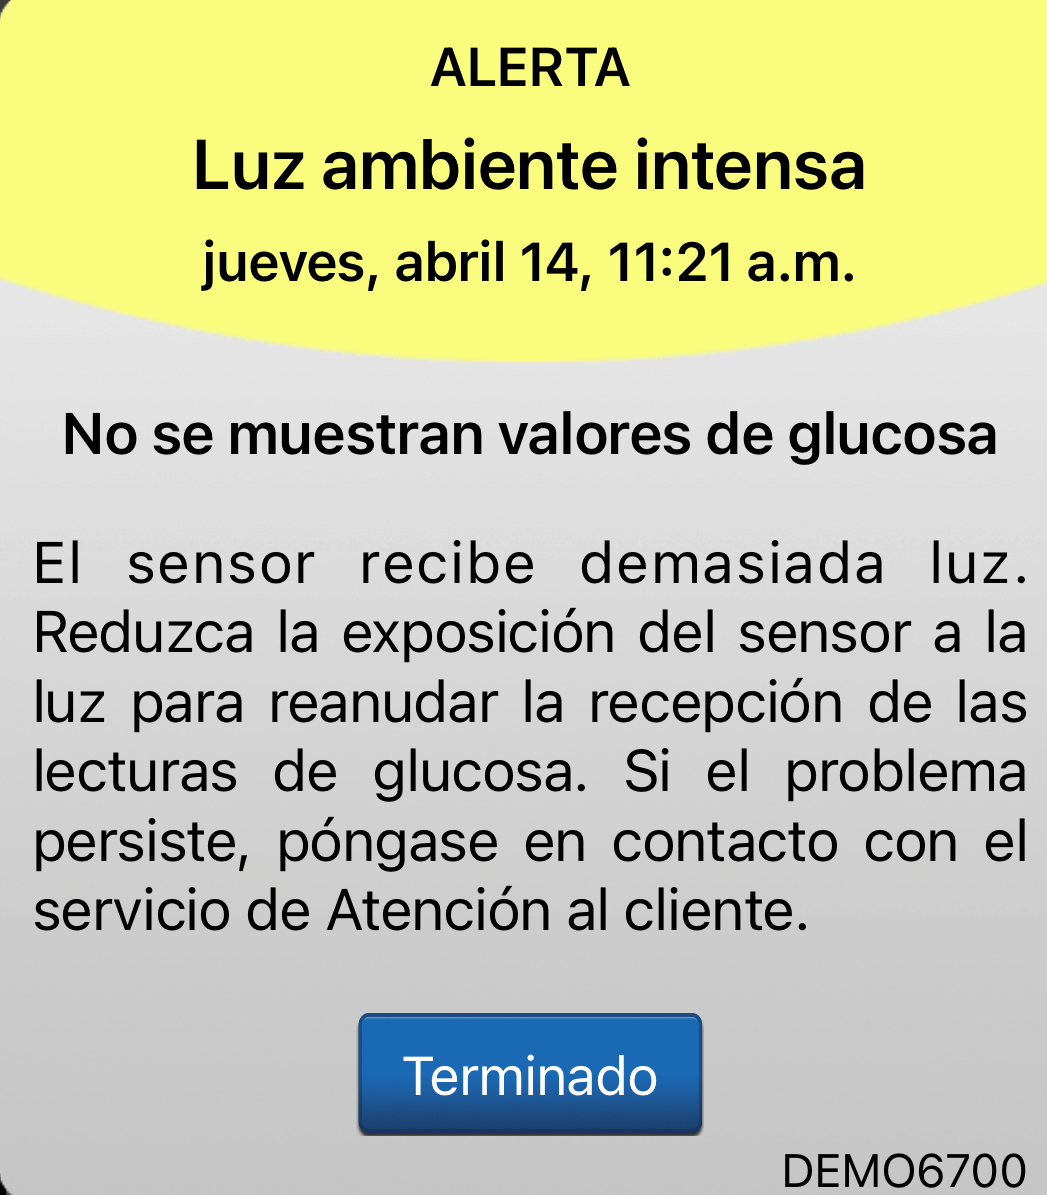

La alerta de luz ambiental es exclusiva del sistema de MCG Eversense®.

Aparecerá si llega demasiada luz al sensor a través de la piel y ello interfiere en la capacidad del sensor para hacer su trabajo. Esta alerta no es frecuente; es una situación temporal.

ALERTA DE LUZ AMBIENTAL

Si recibe esta alerta, puede seguir estos pasos para solucionar el problema:

-

Use algo que cubra el transmisor inteligente y la zona circundante

-

Asegúrese de que el parche adhesivo que tiene colocado en la piel está bien colocado y de que no está levantado por los bordes o plegado. Si lo está, tendrá que sustituir el parche adhesivo.

-

Si utiliza un parche adhesivo transparente, cambie a un parche adhesivo blanco.

-

Intente no exponerse a la luz

solar directa.

ALERTA DE LUZ AMBIENTAL